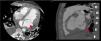

Echocardiographic evaluation (Figure 1) demonstrated posterior mitral leaflet (PML) prolapse with thick-walled aneurysm in the submitral area; cavity size 5.1 × 4.0 cm with to and fro flow into the cavity, with severe mitral regurgitation (MR), no vegetation and thin rim of pericardial effusion. Cardiac contrast-enhanced CT-scan (CECT) (Figure 2) also showed aneurysmal dilatation at the base of the LV along the mitral annulus with prolapse of PML into the left atrium (LA). Both LA and LV were dilated.